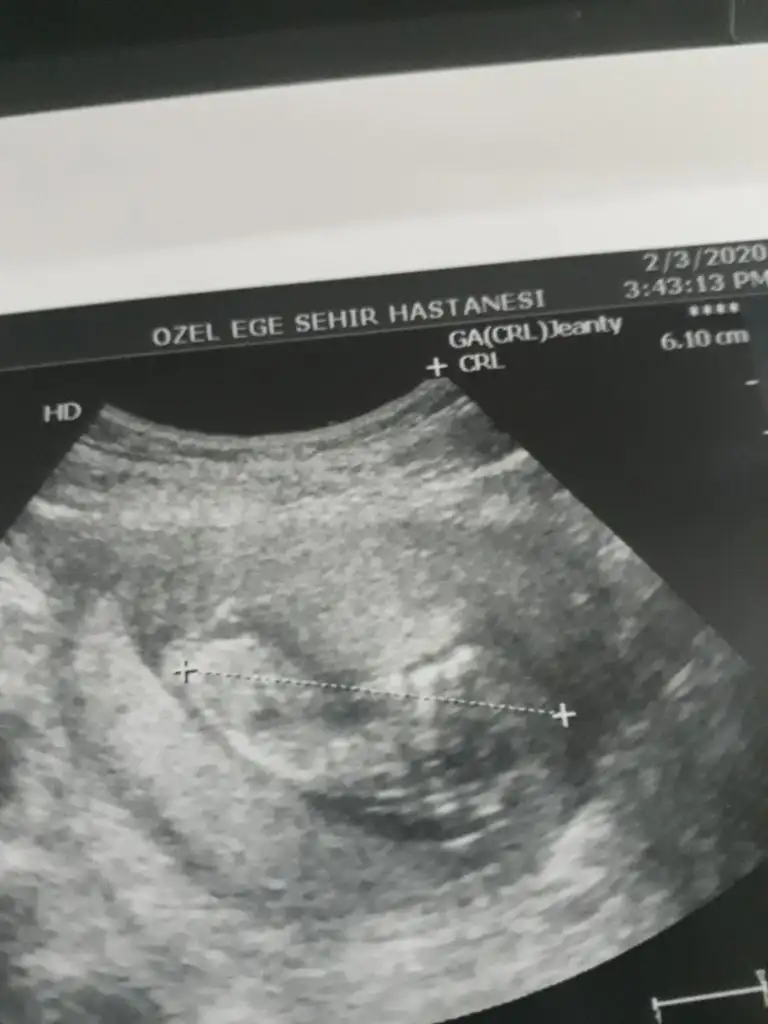

Bu da arkadaşımın bebişinin 12. haftasından görüntüsü. Yine tahmin rica edeceğiz sizden. Sevgiler

• M 12 hafta.webp